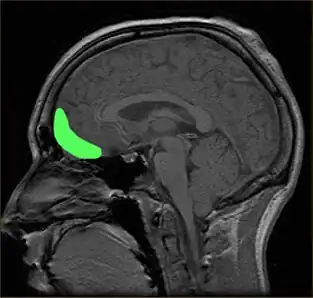

![]() Approximate location of the OFC shown on a sagittal MRI | |

The orbitofrontal cortex (OFC) is a prefrontal cortex region in the frontal lobes of the brain which is involved in the cognitive process of decision-making. In non-human primates it consists of the association cortex areas Brodmann area 11, 12 and 13; in humans it consists of Brodmann area 10, 11 and 47.[1]

The OFC is functionally related to the ventromedial prefrontal cortex.[2] Therefore, the region is distinguished due to the distinct neural connections and the distinct functions it performs.[3] It is defined as the part of the prefrontal cortex that receives projections from the medial dorsal nucleus of the thalamus, and is thought to represent emotion, taste, smell and reward in decision making.[4][5][6][7][8][9][10][11] It gets its name from its position immediately above the orbits in which the eyes are located. Considerable individual variability has been found in the OFC of humans.[12] A related area is found in rodents.[13]